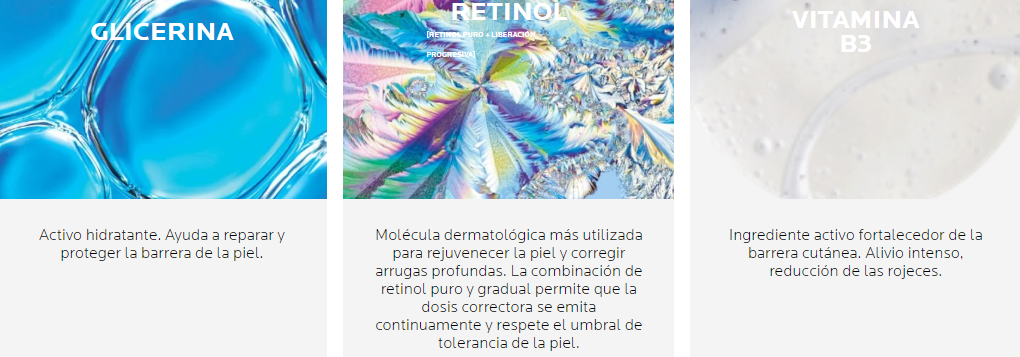

La Roche Posay Serum Retinol B3 30 ml es un suero facial diseñado para combatir los signos visibles del envejecimiento de la piel. Su potente combinación de retinol puro y vitamina B3 actúa en la reducción de arrugas profundas, mejora el tono desigual y aporta un aspecto rejuvenecido a la piel. Este suero es ideal para aquellas personas que buscan revitalizar su piel y conseguir un aspecto más firme y luminoso.

Disfruta de una piel más suave y libre de arrugas con los beneficios transformadores de este suero. Su acción activa mejora visiblemente la textura y luminosidad de la piel, dejándola radiante y uniforme. Además, la vitamina B3 hidrata intensamente evitando la sequedad, mientras reduce la apariencia de líneas finas. Otro gran beneficio es su capacidad para calmar y reducir la irritación gracias a sus propiedades antiinflamatorias.

Corrige arrugas profundas, líneas de expresión y unifica el tono.

Máxima eficacia antiedad correctora garantizando la tolerancia en pieles sensibles.